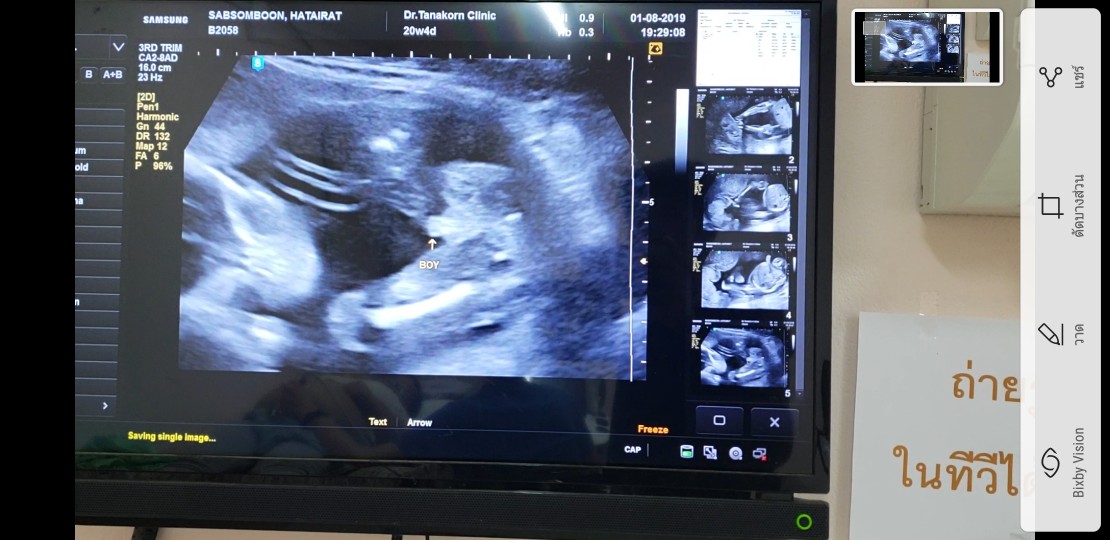

ท้อง5เดือนกว่า

ซาว์ดทั้ง2รอบคุณหมอบอกได้ลูกสาวค่ะ. แม่แอบดีใจมากๆ. คลอดเดือนธันวาคม. แม่ๆบ้านไหนกำหนดคลอดเดือนธันวาบ้างค่ะ ได้ลูกเพศอะไรกัน